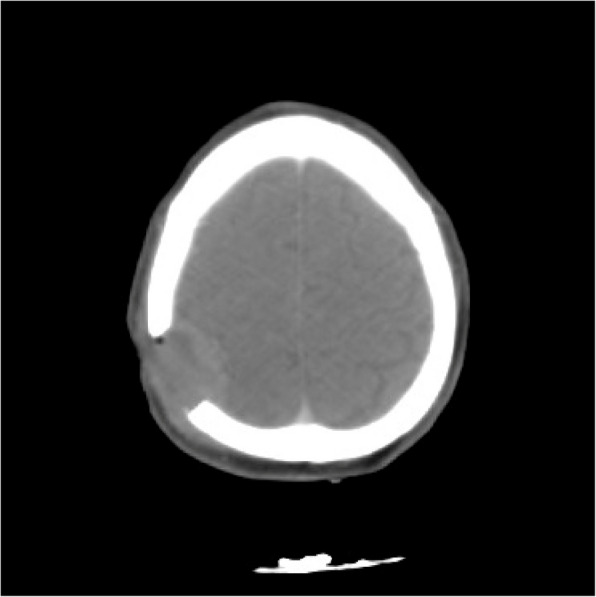

Case description: We present the clinical case of a 57-year-old male patient with a documented history of hepatitis C virus infection but without prior evidence of active hepatocellular carcinoma. Over the course of several months, he developed a non-tender, progressively enlarging mass located in the occipital region of the skull. A computed tomography (CT) scan identified a lytic lesion with intracranial compression, although no midline shift was noted. Histopathological examination confirmed the lesion as metastatic HCC, further supported by immunohistochemical markers Hepatari- 1 and Cytokeratin- 19. Subsequent diagnostic procedures revealed hepatic lesions, including a positron emission tomography (PET)-CT scan. Further examination through CT imaging of the abdomen with contrast highlighted a well-defined focal lesion in hepatic segment 4a, measuring 4.3 × 4.3 cm, predominantly enhancing with HCC characteristics. The skull lesion was surgically removed en bloc, and the patient underwent adjunct radiotherapy and systemic therapy, with palliative therapy till his death in May 2024. To better understand and manage this atypical presentation, we conducted a review for the discussion of clinical manifestations, imaging findings, pathological features, and patient outcomes associated with HCC skull metastases.